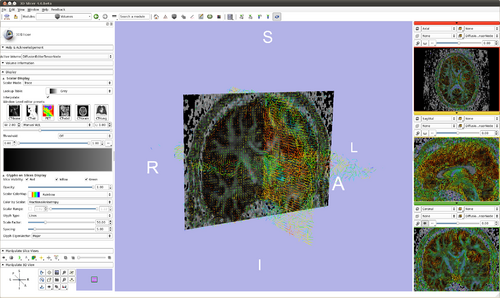

Slicer

Modules